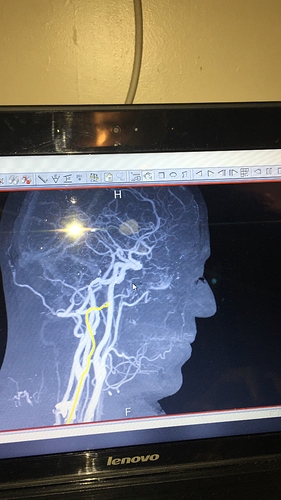

Today, we set date for Endovascular Treatment (Flow Diverter) for July 17th. My annie is 4 x 6.2 and due to the odd/rare shape and how it connect to the opthalmic artery that lead to my left eye, this is the best option FOR NOW! Clipping is not on the table right now as I am on Plavix and Aspirin and they don’t believe Cardiology will agree to stopping either one. I understand this as if they clip the annie, I may end up having a heart attack and Cardiology will likely say “hell no”. Next month will be a year since my heart stent, so there is a possibility I may have been coming off next month but there is no guarantee. On the other hand, since aspirin and Plavix is required for the flow diverter with a requirement for up to at least 6 months, there is a possibility the overlap can give Neurosurgery leverage to level off the aspirin and plavix (only for a couple of weeks for prep and until surgery is over) by that time and do the clipping IF the aneurysm is still active.

As I discussed with my Neurosurgeon, my goal is to control/manage this annie ASAP using the best treatment with the best outcome. He said with my annie there is a 0.5% chance of rupture over the next year. My annie as stated above is oddly shaped which is complicated in terms of risking vision loss. The annie itself is like a bubble but the neck is like a double bubble. It look like a hand is clasped over the annie and it is directly connected to the opthalmic artery. I told my husband that is God’s hand holding my annie! Coiling is off the table as if they filled it with coils, they could possibly fall out and if it clot that clot could easily travel in either direction and cause a stroke. I am comfortable with what we have planned as this is the best option for right now until we can do a clipping, if needed. He indicated there was a good chance the annie could shrink. He said, the primary goal of the flow diverter is to take the pressure off the annie which will ultimately reduce the chance of rupture. I am in good hands with some of the best doctors in the country and I trust their recommendation. Hubby took notes so if I forgot something I will post later once he type them out for me as I cannot read his “doctor” style writing. LOL